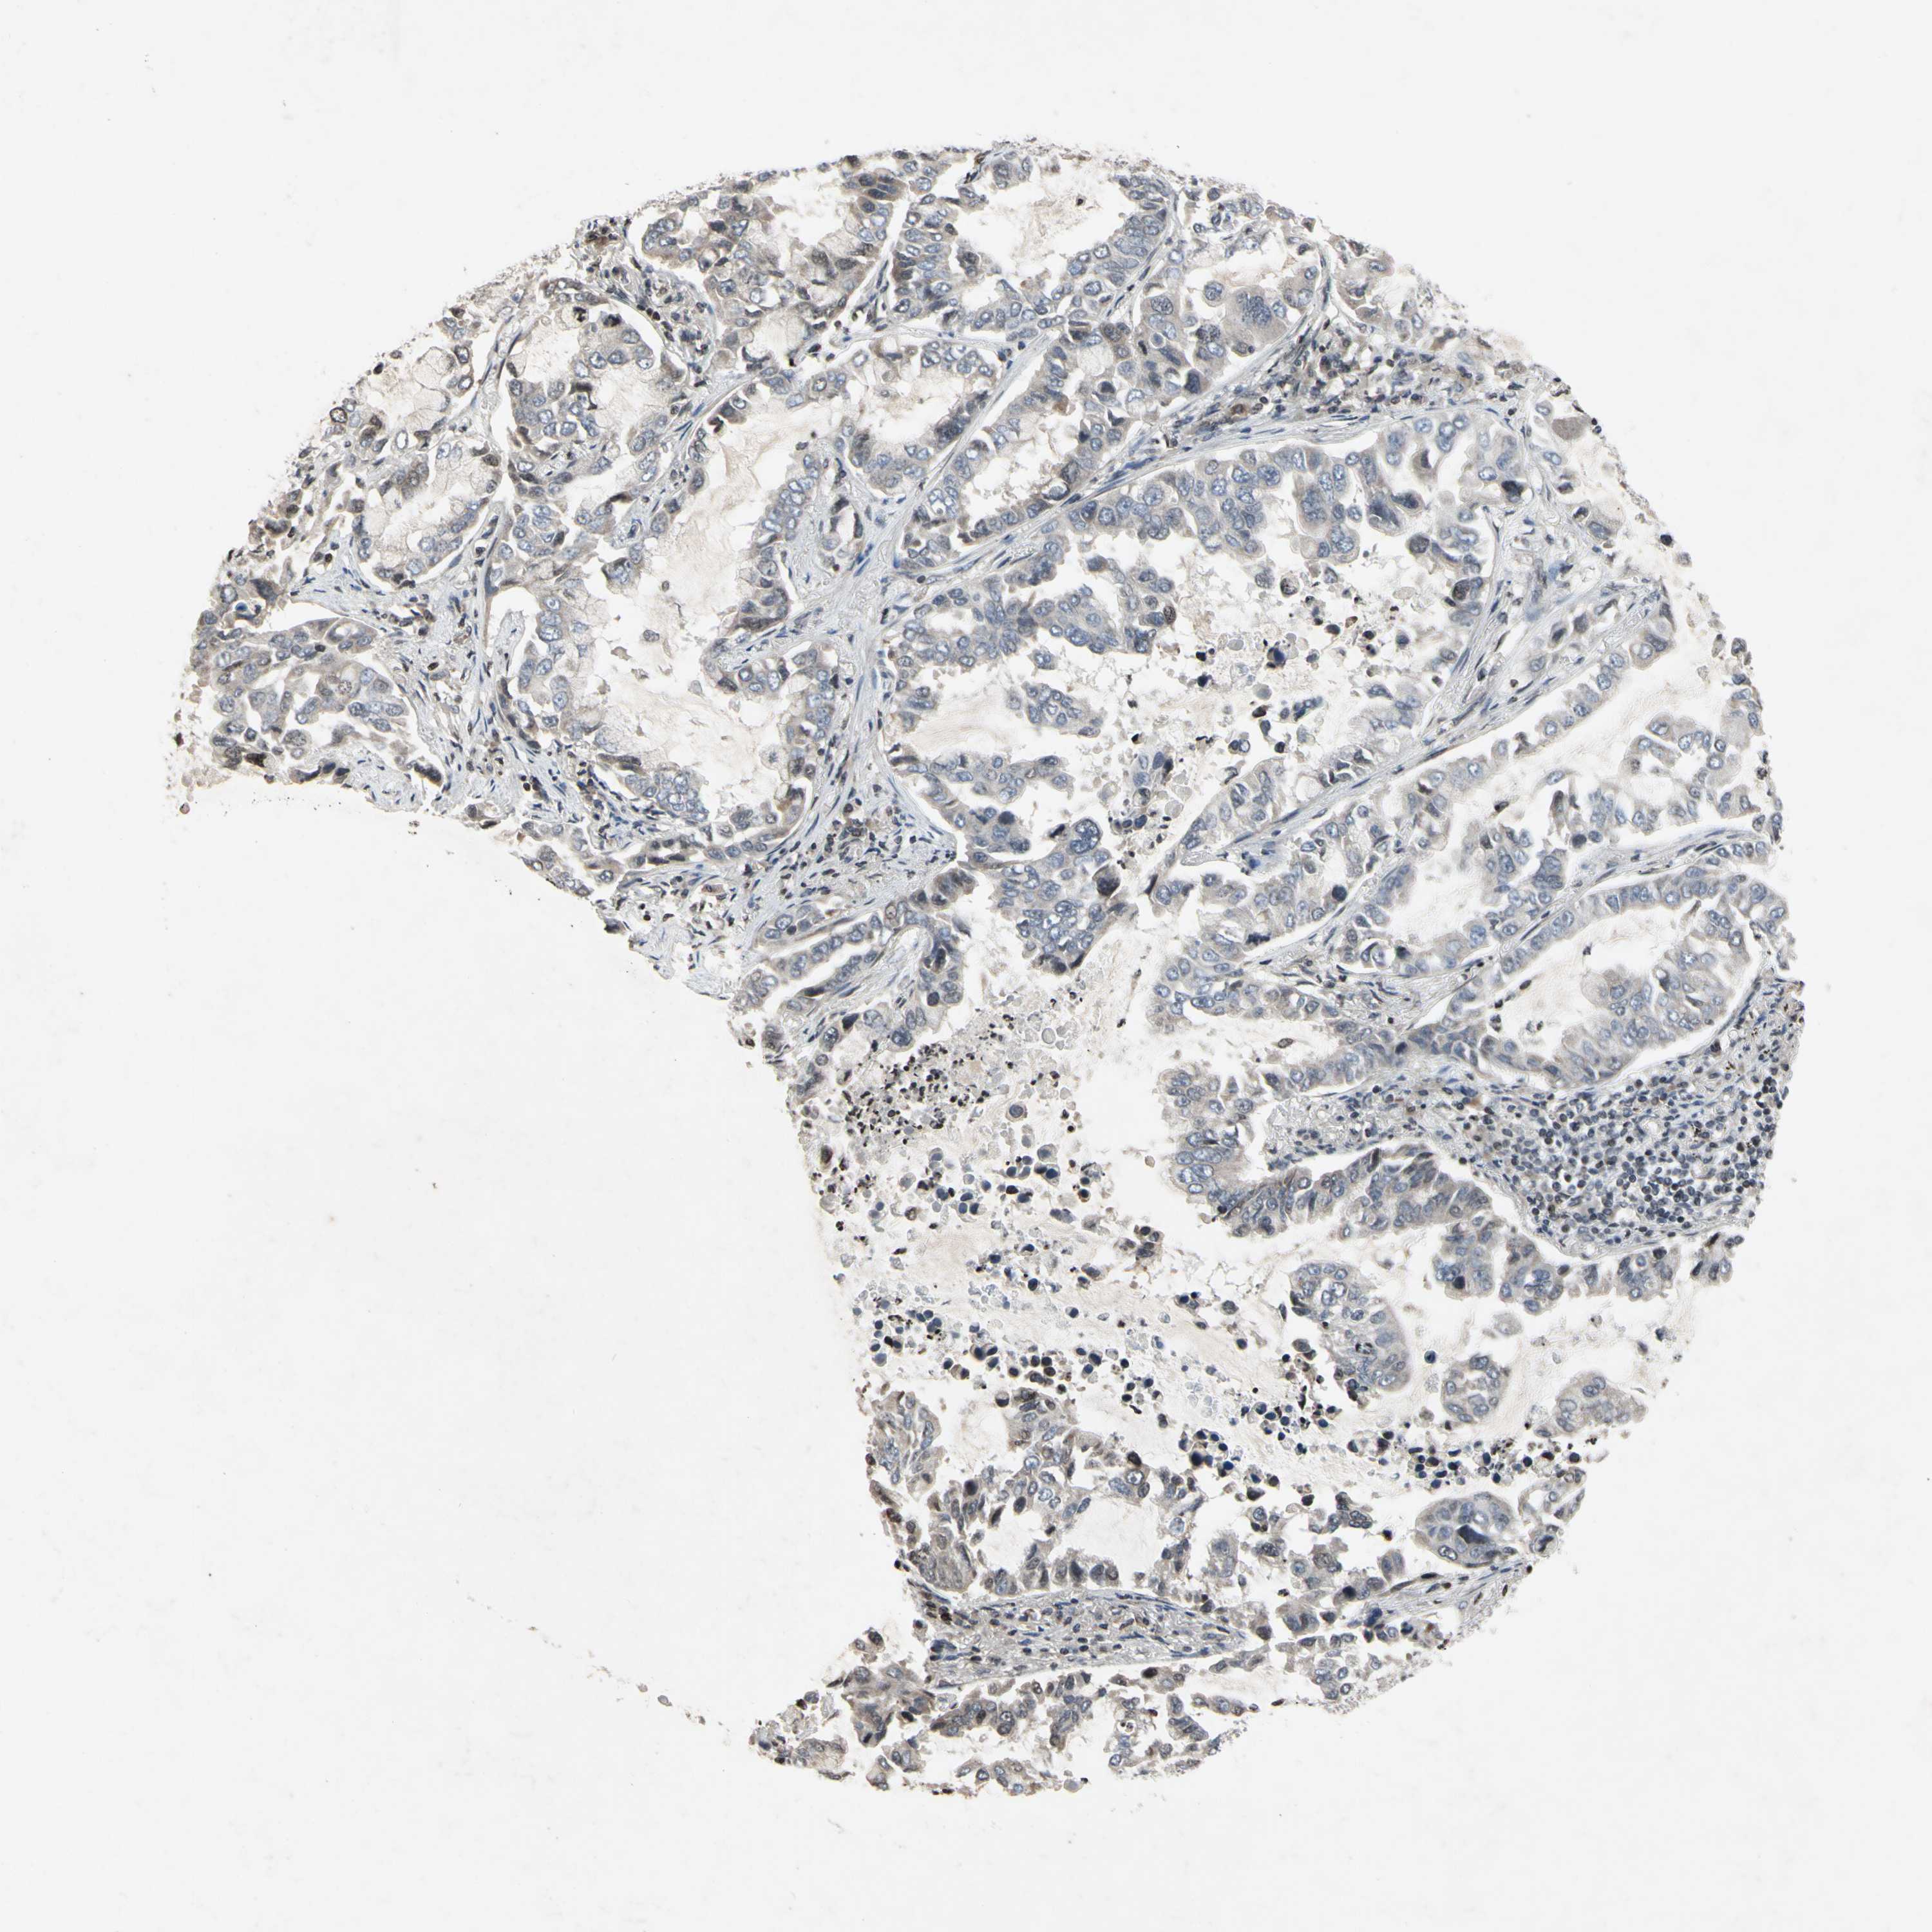

LUNG SQUAMOUS CELL CARCINOMA (TCGA) - Interactive survival scatter ploti

The Survival Scatter plot shows the clinical status (i.e. dead or alive) for all individuals in the patient cohort, based on the same data that underlies the corresponding Kaplan-Meier plots. Patients that are alive at last time for follow-up are shown in blue and patients who have died during the study are shown in red.

The x-axis shows the expression levels (FPKM) of the investigated gene in the tumor tissue at the time of diagnosis. The y-axis shows the follow-up time after diagnosis (years). Both axes are complimented with kernel density curves demonstrating the data density over the axes. The top density plot shows the expression levels (FPKM) distribution among dead (red) and alive patients (blue). The right density plot shows the data density of the survived years of dead patients with high and low expression levels respectively, stratified using the cutoff indicated by the vertical dashed line through the Survival Scatter plot. This cutoff is automatically defined based on the FPKM cutoff that minimizes the p-score. The cutoff can be changed by dragging the vertical line or by entering a cutoff value in the square labeled "Current cut-off".

Under the Survival Scatter plot the p-score landscape (black curve; left axis) is shown together with dead median separation (red curve; right axis). Dead median separation is the difference in median mRNA expression between patients who have died with high and low expression, respectively. It is calculated as follows: median FPKM expression of dead patients with high expression - median FPKM expression of dead patients with low expression. This is intended to aid the user in visually exploring custom cutoffs and the associated p-scores and dead median separation.

Individual patient data is displayed and can be filtered by clicking on one or more of the category buttons on the top of the page. Categories describing expression level and patient information include: high, low, alive, dead, female, male and tumor stages. The scale of the x-axis can be toggled between linear and log-scale by clicking on the "x log" button. Mouse-over function shows TCGA ID, patient information and mRNA expression (FPKM) for each patient.

& Survival analysisi

Kaplan-Meier plots summarize results from analysis of correlation between mRNA expression level and patient survival. Patients were divided based on level of expression into one of the two groups "low" (under cut off) or "high" (over cut off). X-axis shows time for survival (years) and y-axis shows the probability of survival, where 1.0 corresponds to 100 percent.

ARG1 is not prognostic in Lung Squamous Cell Carcinoma (TCGA)

TCGA RNA samplesi

RNA-seq data is reported as average FPKM (number Fragments Per Kilobase of exon per Million reads), generated by the The Cancer Genome Atlas (TCGA) .

Normal distribution across the dataset is visualized with box plots, shown as median and 25th and 75th percentiles. Points are displayed as outliers if they are above or below 1.5 times the interquartile range. FPKM values of the individual samples are presented next to the box plot.

Average pTPM 0.6

Number of samples 489